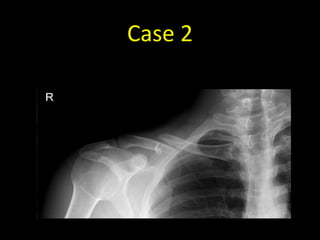

Case 2

• 27 year old with pain in the right shoulder after a

• AP radiograph of the right

shoulder

• There is a completely

displaced comminuted

fracture of the right clavicle at

the junction of the middle

and lateral thirds

• The fracture is described as

comminuted as there are

three separate fracture

fragments (arrows)